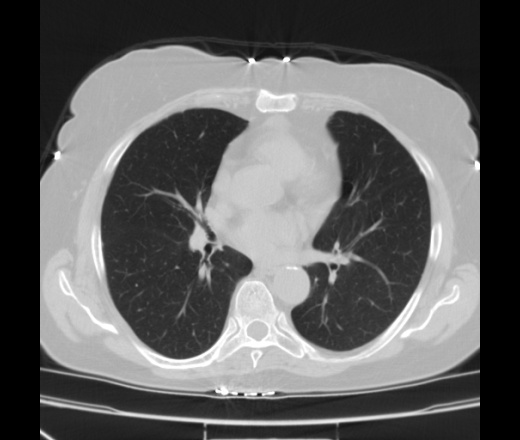

Женщина средних лет. Выраженные кардиалгические боли за грудиной, ранее не беспокоили, ни с чем не связывает, была доставлена в ОКЦ с подозрением на ОКС. Обследована, данных за ОКС нет. Перенаправили к нам с грудным остеохондрозом. Вариантов не было, госпитализировали. Невропатологи машут рукама, мол с какаих пор корешковый синдром с грудины начинается, не наша она. Консилиумом решено сделать КТ, зачем, сами не знают. ЭКГ б/о, кровь б/о. На ЭхоКГ у нас нашли какую то структуру в перикарде в области левого желудочка то ли жидкость, то ли жир, то ли сдавление из вне (по УЗИ я не разбираюсь, это со слов кардиолога который проводил исследование). Меня смущают только элементы жидкостной плотности обозначенные стрелками, их плотность от 0 до +7 Ед.Н.

К второму снимку я возможно зря придрался, думаю это просто жидкость в перикарде которая там и  в норме есть.

Ну и жидкость и что? Если и есть медиастинит или перикардит он болеть не будет. Расширена левая легочная артерия. Тромбоэмболия? Я бы сделал с контрастом. При кардиологических исследованиях можно подключать ЭКГ-слежение и делать на кардиопрограмме. Тогда картинка будет лучше.